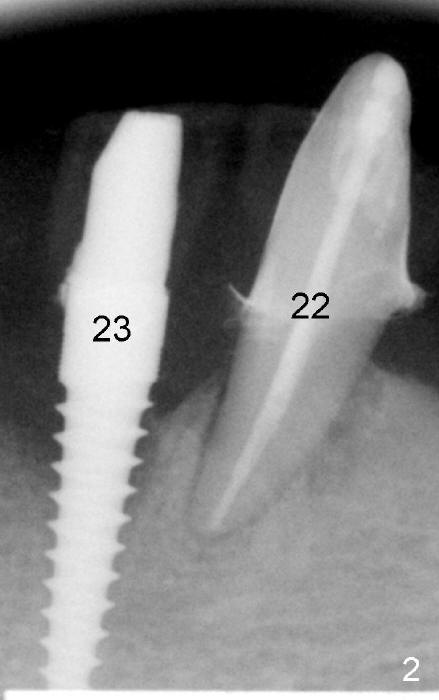

A 73-year-old lady has an existing upper complete denture and a lower flipper. A few days after #23 exfoliation, a 3.5x17 mm one piece implant is placed (Fig.1) and an immediate provisional is fabricated. Later the lower flipper is remade. The one piece implant and the provisional have been doing well for 7 months by the time Fig.2 is taken.